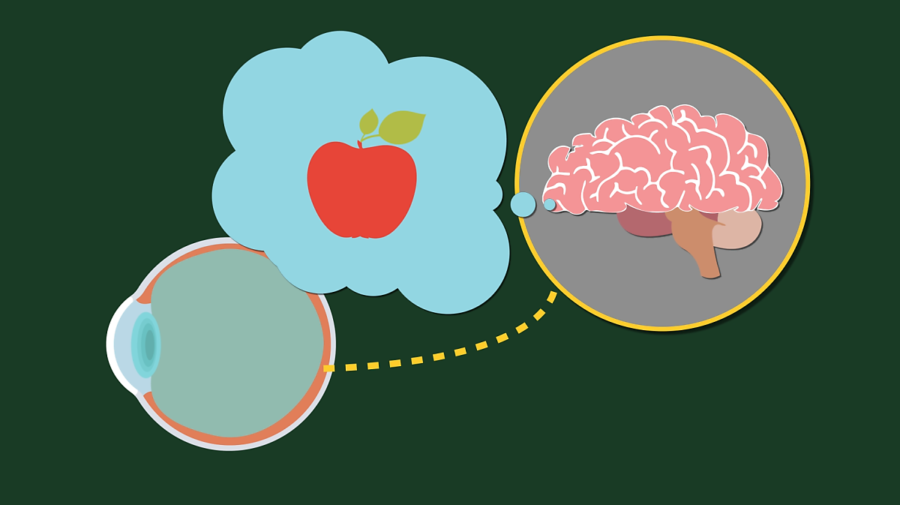

주제의 의문을 해결하려면 눈이 세상을 어떻게 볼 수 있는지부터 알아야 합니다. 눈의 인식 과정을 보면 물체에서 반사된 빛이 눈에 도달하는 것부터 시작합니다. 빛은 수정체에 의해 굴절되어 망막의 한 점에 초점을 맞추고, 망막의 광수용기가 빛을 전기 신호로 변환해 시신경을 통해 뇌로 전달합니다.

그러면 뇌가 전기 신호를 처리해 상을 생성하여 물체를 인식할 수 있도록 해주는데, 망막에 상이 제대로 맺히지 않으면 당연히 제대로 인식할 수가 없습니다. 물체의 상이 망막에 제대로 맺히지 못하고, 망막의 앞쪽 또는 뒤쪽에 맺히는 사람을 근시, 원시, 난시 등으로 진단합니다.